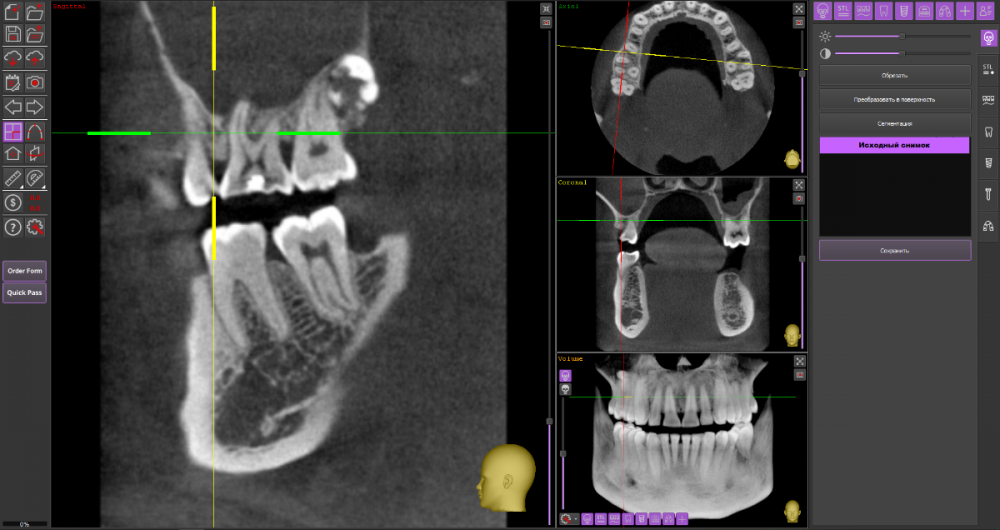

Mnrg Опубликовано 6 июля, 2023 Поделиться Опубликовано 6 июля, 2023 Всех приветствую! Беспокоит правосторонний гайморит и тонзиллит. Сделали КТ, нашли восьмерку, но предложили вместо удаления восьмерки депульпировать шестерку, консилиум сошелся во мнении, что корень перфорирует пазуху и пломба слишком близко к нерву, возможно воспаление. При зондировании между 6 и7 слегка побаливает десна, шестерка не беспокоит, холод чувствует, но не болит. Восьмерку предложили оставить. Спорить не стал, лишь решил собрать воедино мнения специалистов, т.к ближайшие более менее нормальные клиники от 100км. Архив с файлами КТ прикрепил, прошу специалистов глянуть и поделиться мнением, с чего все-таки начать, помочь разобраться.Archive.rar Ссылка на комментарий

wladdX Опубликовано 7 июля, 2023 Поделиться Опубликовано 7 июля, 2023 (изменено) Гайморит у вас совершенно необязательно имеет одонтогенную природу (вызван зубами). Судя по КТ, зуб 16 может быть виновником (а может и не быть). Для уточнения нужна также проверка витальности его пульпы (жив нерв или нет). Если пульпа нежизнеспособна, то этот зуб почти наверняка поддерживает воспалительный процесс в пазухе. Зуб 18 вряд ли нужно трогать. Лежит он себе в кости и пускай, никому он там не вредит. Да он вплотную прилежит к корням зуба 17, но и только. С внешней средой не контактирует. Никакого негативного влияния на соседние зубы он оказывать не должен: формирование корней завершено, потенции к росту и какому-либо движению нет. Удаление зуба 18 в данной ситуации вряд ли оправдано. Процедура не самая простая, но и не запредельной сложности. Изменено 7 июля, 2023 пользователем wladdX Ссылка на комментарий

Mnrg Опубликовано 7 июля, 2023 Автор Поделиться Опубликовано 7 июля, 2023 6 минут назад, wladdX сказал: Гайморит у вас совершенно необязательно имеет одонтогенную природу (вызван зубами). Судя по КТ, зуб 16 может быть виновником (а может и не быть). Для уточнения нужна также проверка витальности его пульпы (жив нерв или нет). Если пульпа нежизнеспособна, то этот зуб почти наверняка поддерживает воспалительный процесс в пазухе. Зуб 18 вряд ли нужно трогать. Лежит он себе в кости и пускай, никому он там не вредит. Да он вплотную прилежит к корням зуба 17, но и только. С внешней средой не контактирует. Никакого негативного влияния на соседние зубы он оказывать не должен: формирование корней завершено, потенции к росту и какому-либо движению нет. Удаление зуба 18 в данной ситуации вряд ли оправдано. Процедура не самая простая, но и не запредельной сложности. Шестерку проверяли холодом - чувствует, не знаю, означает ли это жизнеспособность пульпы, но на холод реагировал немного сильней других зубов. Сегодня открыл КТ программой RadiAntViewer и обнаружил в 3D просмотре визуальные признаки нахождения части восьмерки в краю пазухи. Конечно я не могу утверждать, т.к не врач и насколько понимаю это режим моделирования, но все же выглядит убедительно на мой скромный взгляд. Еще один глупый вопрос, если позволите) Возможно ли в шестерке в одном из трех корней воспаление и нерв разрушен, а другие два при этом будут создавать чувствительность, т.е быть "живыми" или же это фантастика? Деньги запросили немалые для нашего региона за депульпацию (13к) поэтому пытаюсь собрать как можно больше информации прежде, чем принимать решения. Ссылка на комментарий

wladdX Опубликовано 8 июля, 2023 Поделиться Опубликовано 8 июля, 2023 Ничего нового добавить к своим словам я не могу. Разве что повторить : "Гайморит у вас совершенно необязательно имеет одонтогенную природу". Т.е. надо рассматривать возможность ЛОР-патологии в чистом виде. Если зуб 16 с живой пульпой, то других одонтогенных причин при помощи данного КТ исследования я не вижу. На истину в последней инстанции не претендую. 1 1 Ссылка на комментарий